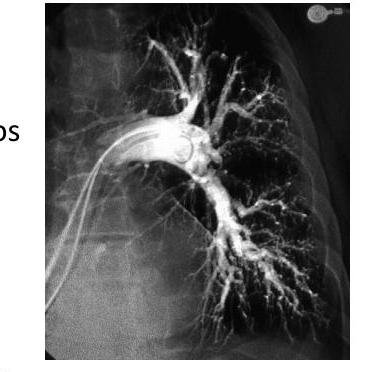

# ENFERMEDAD TROMBOEMBÓLICA ## DEFINICIÓN El término trombosis se refiere a la formación de una masa anormal dentro del sistema vascular a partir de los componentes sanguíneos. La **Enfermedad Tromboembólica Venosa (ETV)** comprende un espectro de enfermedades que engloban la **Trombosis Venosa Profunda (TVP)** y la **Tromboembolia Pulmonar (TEP)**; ambas comparten los mismos factores predisponentes. La TVP es una oclusión de los vasos pulmonares debido a un coágulo sanguíneo; el **95%** de los casos ocurre en el sistema venoso profundo de los miembros inferiores y posteriormente el émbolo se deposita en el área pulmonar. Cuando una TVP proximal no es tratada, ocurre una TP en el **33%** de los casos y otro **33%** presenta un embolismo subclínico. Otros orígenes de émbolos son las venas pélvicas, las extremidades superiores y las cavidades cardíacas derechas.  # FISIOPATOLOGÍA El proceso de trombosis involucra diversos factores que predisponen a un individuo a sufrir una oclusión trombótica, los cuales fueron descritos por Virchow desde el siglo XIX. ## TRÍADA DE VIRCHOW: - Lesión endotelial (Trauma, cirugía, fractura reciente, evento previo de TVP) - Éstasis o alteración del flujo sanguíneo (inmovilidad, obesidad, ICC, aumento PVC) - Estado hipercoagulable de la sangre (embarazo, postparto, ACO, cáncer, quemaduras severas) ## Triada de Virchow  Durante el episodio agudo se pueden apreciar las siguientes alteraciones fisiopatológicas: 1. Alteración del intercambio gaseoso: **AUMENTO DEL ESPACIO MUERTO FISIOLÓGICO** (zona que está siendo ventilada, pero no perfundida) por desequilibrio V/Q en el pulmón no obstruido (más perfusión que ventilación) y por shunt derecha a izquierda, que puede ocurrir a nivel intrapulmonar o intracardíaco. 2. Hiperventilación alveolar por estímulo reflejo nervioso. 3. Aumento de la resistencia al flujo aéreo por broncoconstricción de las vías aéreas distales al bronquio obstruido. 4. Disminución de la distensibilidad pulmonar por edema, hemorragia o pérdida de surfactante. 5. Aumento de la resistencia vascular pulmonar por obstrucción vascular o liberación de agentes neurohumorales como la serotonina por las plaquetas. 6. Disfunción ventricular derecha. El fracaso ventricular derecho es la causa de muerte más habitual de la TEP. A medida que aumenta la resistencia vascular pulmonar, aumenta la tensión del VD, mayor dilatación y disfunción ventricular. # EPIDEMIOLOGÍA - La ETV está ubicada en el 3er lugar como causa de muerte cardiovascular (después de enfermedad coronaria e isquemia cerebral). - Es un trastorno multifactorial, con incidencia anual de 1-2 por cada 1,000 personas. - Más frecuente en hombres. - Asociada a la edad con incremento a 1 por cada 100 personas en mayores de 55 años. - Un 20 % de quienes padecen ETV no tienen factores de riesgo asociados. FACTORES DE RIESGO | RIESGO | ANTECEDENTE | | :-------- | :--------------------------------------------------------------------------------- | | **ALTO** | Fractura de cadera o miembros inferiores <br> Cirugía **ORTOPÉDICA** <br> Prótesis de cadera <br> Cirugía mayor <br> Politrauma <br> IAM <br> Lesión de médula espinal | | **MODERADO** | Artroscopia <br> Catéter central <br> Quimioterapia <br> Insuficiencia cardíaca congestiva <br> Tratamiento hormonal <br> Embarazo <br> Trombofilia | | **BAJO** | Reposo en cama <br> Inmovilidad <br> Edad avanzada <br> Laparoscpia <br> Obesidad <br> Venas varicosas <br> Viajes en avión de largo recorrido <br> Síndrome antifosfolípido <br> Hiperhomocisteinemia <br> Policitemia primaria <br> EPOC | La resistencia a la proteína C activada (Factor V de Leiden) es el estado de hipercoagulabilidad hereditario más frecuente en el TEP, seguido de las mutaciones del gen de la protrombina. Pero estos factores genéticos solo justifican 1/5 casos de TEP y la mayoría de los que tienen estos factores genéticos nunca desarrollan ETV. # CLÍNICA ## TVP **DOLOR EN LA PANTORRILLA**: de inicio insidioso, que tiende a empeorar con el tiempo y se acompaña de palpación dolorosa. - La TVP masiva es fácil de reconocer. El paciente presenta **EDEMA DE MUSLO** con palpación dolorosa en zona inguinal y sobre la vena femoral común. - La TVP de miembros superiores puede producir empastamiento de la fosa supraclavicular, aumento de diámetro del miembro o circulación colateral en la región anterior del tórax. ## TEP **DISNEA**: generalmente súbita, es el síntoma más frecuente. Puede aparecer síncope o hipotensión brusca de causas no aclaradas. **DOLOR PLEURÍTICO**: aparece posterior a la disnea, siendo el segundo síntoma más frecuente. Taquicardia y Taquipnea: son signos constantes. Otros: hemoptisis, opresión torácica, broncoespasmo. | | | | :--------------- | :------------------------------------------------------------------------ | | **TEP Masivo** | Se presenta con hipotensión o choque. Suele ser TEP de gran tamaño o difusos. | | **TEP Moderado / Grande** | Sin hipotensión ni choque <br> Signos ecocardiográficos de sobrecarga de VD o elevación de marcadores de daño miocárdico | | **TEP Moderado / Pequeño** | Tensión arterial y función ventricular derecha normales. | # DIAGNÓSTICO ## PROBABILIDAD CLÍNICA La estimación de la probabilidad clínica es el primer eslabón en la aproximación diagnóstica del TEP. El diagnóstico es difícil debido a lo inespecífico de la clínica. Lo primero que se debe hacer es determinar la probabilidad clínica, pues una probabilidad clínica baja de TVP o moderada/baja de TEP permiten descartar la enfermedad si el Dímero D es negativo sin utilizar otras pruebas de imagen. Dada la gravedad del proceso, un alto grado de sospecha clínica basta para iniciar anticoagulante. ## SISTEMA DE WELLS DE PROBABILIDAD CLÍNICA | Síntomas o signos de Trombosis Profunda | 3 | | :------------------------------------------------------------ | :-- | | Diagnóstico alternativo menos probable | 3 | | FC >100 lpm | 1.5 | | Cirugía o inmovilización en las 4 semanas previas | 1.5 | | Episodio de tromboembolismo pulmonar o trombosis profunda previa | 1.5 | | Hemoptisis | 1 | | Cáncer | 1 | | PROBABILIDAD BAJA | 0-1 punto | | :---------------------- | :----------- | | PROBABILIDAD INTERMEDIA | 2-6 puntos | | PROBABILIDAD ALTA | >7 puntos | ## RADIOGRAFÍA Una placa normal o con escasas alteraciones aumenta la sospecha de TEP, aunque lo habitual es que existan anomalías: - Elevación del hemidiafragma. - Atelectasias. - Anomalías parenquimatosas pulmonares. - Derrame pleural escaso y serohemático. **SIGNO DE WESTERMARK**: Oligohemia focal que produce hipertensión pulmonar. **JOROBA DE HAMPTON**: condensación parenquimatosa triangular de base pleural. Asociado a TEP con infarto y presenta derrame pleural de pequeña cuantía.  # ELECTROCARDIOGRAMA Las alteraciones más comunes son Taquicardia Sinusal y Anomalías Inespecíficas en el ST-T de V1 - V4. Puede haber signos de sobrecarga derecha como patrón SI,QIII,TIII (S en la derivación I, Q y T invertida en la III). ## LABORATORIO Marcadores Cardíacos: La elevación de Troponinas aumenta el riesgo de complicaciones y mortalidad en TEP estables. Gasometría: existe hipoxemia y aumento de gradiente alveoloarterial. - Puede haber pacientes sin antecedentes de patología pulmonar con PO2 y D(a-a)O2 normales. - La PaCO2 suele estar baja (hipoventilación refleja) - **ALCALOSIS RESPIRATORIA**. ## DÍMERO D Sensibilidad del **95%** (85%-99%) y especificidad del **50%** (29-71%) y un valor predictivo negativo del 95 al 100 %. Son generados por la acción del Factor VIII de coagulación sobre los monómeros y multímeros de fibrina. Su elevación revela la presencia de fibrinólisis endógena, pero no es específico de TEP. Aumenta también en: IAM, neumonía, fallo derecho, carcinomas, cirugía, inmovilizaciones. Se debe determinar mediante **ELISA**. Tiene un elevado valor predictivo negativo, especialmente si se combina con la probabilidad clínica del Sistema Wells - Probabilidad Baja/Intermedia y Dímero D <500 \rightarrow se descarta TEP. No es muy útil en pacientes con cáncer o cirugía reciente ya que la mayoría tiene >500 ng / ml. ## TAC ESPIRAL CON CONTRASTE ## 1ª elección: ante la sospecha de TEP - Tiene sensibilidad mayor del **80 %** y una especificidad mayor del **90 %**. - Visualiza arterias del sexto orden. - Tiene contraindicación en la IR o alergia al contraste. Si el resultado es normal y la sospecha clínica es alta - **ANGIOGRAFÍA PULMONAR**. ## ANGIOGRAFÍA PULMONAR - Era el **GOLD STANDARD** hasta antes de la APTC. - Puede precisarse para el diagnóstico cuando hay una alta sospecha clínica y los otros estudios (TC Espiral, Ecografía) son negativos. - Se debe realizar en pacientes que se vayan a someter a algún tipo de intervención como una embolectomía o una trombolisis dirigida por catéter. # ANGIOGRAFÍA POR TOMOGRAFÍA La **APTC** es la prueba que actualmente se considera **GOLD ESTÁNDAR** al ser menos invasiva. ## GAMMAGRAFÍA DE PERFUSIÓN PULMONAR  - Prueba de segunda línea, indicada en casos en los que no se pueda realizar la Tomografía. - Un resultado normal excluye el diagnóstico de TEP. - Un resultado anormal, se debe combinar con el de la gammagrafía de ventilación y así determinar la probabilidad gammagráfica de TEP. - Una gammagrafía de alta probabilidad diagnóstica es la que presenta 2 o más defectos de perfusión segmentarios con gammagrafía de ventilación y radiografía de tórax normales. ## ECOCARDIOGRAFÍA - Baja sensibilidad para detectar TEP, puede ser útil en casos de sospecha de TEP clínicamente graves, puesto que valora la función ventricular derecha y visualiza trombos importantes. - Se realiza transesofágica o transtorácica. ## ECOGRAFÍA VENOSA - Es la prueba no invasiva más utilizada en la actualidad para valorar TVP y ha llevado al desuso a la pletismografía y a la flebografía isotópica. - Es fiable en sintomáticos ambulatorios con sospecha de TVP; en sintomáticos y hospitalizados, pero la tasa de detección de TVP es mucho más baja. | | | | :------------------- | :------------------------------------------------------------------------------------------ | | **TROMBO NO MASIVO** | Presenta un excelente pronóstico y es la más frecuente. | | **TROMBO SUB-MASIVO** | Presenta disfunción del ventrículo derecho del corazón, pero con una presión arterial normal. | | **TROMBO MASIVO** | Afectación de al menos la mitad de los vasos del pulmón. | # TRATAMIENTO El tratamiento primario consiste en la disolución del coágulo, ya sea mediante trombolisis o mediante embolectomía. La anticoagulación o el filtro de vena cava constituyen más bien una prevención secundaria a un nuevo episodio. - El tratamiento anticoagulante es el factor más importante en la terapéutica de ETV. ## HEPARINAS ## HEPARINA NO FRACCIONADA (HNF) - Acelera la acción de la antitrombina III e inactiva el factor Xa, por lo que se **previene la formación de un trombo adicional** y permite que la fibrinolisis endógena disuelva algo del émbolo. - Requiere monitorizar **TTPa**, que debe duplicarse. - Su acción puede ser revertida con **SULFATO DE PROTAMINA**. - Se utiliza fundamentalmente en TEP con compromiso hemodinámico junto a los fibrinolíticos. ## HEPARINA DE BAJO PESO MOLECULAR (HBPM) - Se administra por vía subcutánea. - Tiene una vida media plasmática más larga, ya que interactúa menos con las plaquetas y las proteínas. - Apenas se unen a la antitrombina III y ejerce su efecto fundamentalmente inactivando el factor Xa. - La monitorización del TTPa y el ajuste de dosis no suele ser necesaria, salvo en casos de obesidad, embarazo o IR grave. - En situaciones hemodinámicamente estables es tan eficaz y segura como la HNF. ## FONDAPARINUX Es un inhibidor selectivo del factor Xa que se administra por vía subcutánea una sola vez al día. No necesita controles de coagulación, pero debe reducirse su dosis en IR. # ANTICOAGULANTES ORALES Inhiben la activación de los factores de coagulación dependientes vitamina K (II, VII, IX y X). ## Fármaco más utilizado - WARFARINA - Se administra desde el día siguiente del inicio de la heparina y se mantiene simultáneamente durante al menos 5 días. - El mantenimiento requiere de un **INR entre 2-3**. - Si el paciente está hemodinámicamente estable y con adecuada función del Ventrículo derecho, los anticoagulantes son suficientes para buenos resultados. **CONTRAINDICADOS EN EL EMBARAZO** por teratogenia de los cumarínicos. El acenocumarol junto con la HNF se inicia hasta después del parto, independientemente de la heparina utilizada. ## TROMBOLÍTICOS 1ª elección en **TEP MASIVO** (única indicación aprobada) y en la TVP Iliofemoral masiva o de cava inferior. - Debe realizarse de forma precoz, aunque puede haber respuesta hasta 2 semanas tras el TEP. - Objetivo: rápida lisis del trombo, acortando la fase de alto riesgo y reduciendo la mortalidad. - Fármacos empleados: Urocinasa, Estreptocinasa, Activador Tisular del Plasminógeno (rTPA). ## TRATAMIENTO INVASIVO Colocación de filtros en la cava inferior, embolectomía (si hay compromiso hemodinámico grave que no responde a fibrinolíticos) o la tromboendarterectomía (en los casos de hipertensión pulmonar crónica secundaria a TEP con clínica grave). ## Indicaciones del filtro en cava inferior: - Contraindicaciones o complicaciones de anticoagulación en pacientes con ETV o alto riesgo de la misma. - TEP recurrente a pesar de anticoagulación. - Gran trombo flotante en vena cava inferior. - Realización simultánea de embolectomía o tromboendarteriectomía. - Profilaxis en riesgo extremo. Los filtros evitan TEP en la fase aguda, pero a largo plazo aumentan el riesgo de TVP, por lo que los pacientes que lo usen, deben permanecer anticoagulados. ## DURACIÓN DE ANTICOAGULANTES Se recomienda **3 - 6 meses** cuando es el primer episodio en pacientes con factores de riesgo reversibles. En caso contrario, mantenerlo indefinidamente, valorando periódicamente si el riesgo de sangrado supera al beneficio de la anticoagulación.  # DIAGNÓSTICO TEP  (c) Copyright 2021-2022 Joyas ENARM - Todos los derechos reservados -